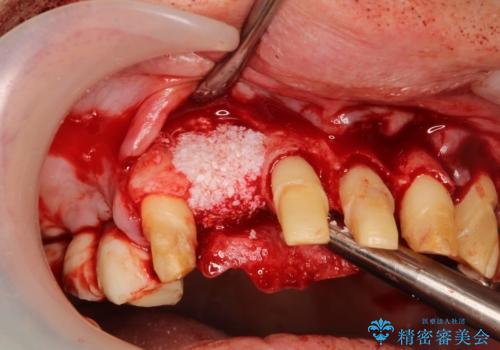

- 歯周病により欠損が生じた歯槽骨、まずは再生治療をおこなう

→治癒後、確定外科を行い完全に歯周ポケットを除去し、最終的に歯周補綴をおこなう

- 歯周組織再生治療は患者様の状態によって術後の経過が異なります(見た目が改善しない場合もあります)

- 歯周組織再生治療は自費診療(保険適用外)となります